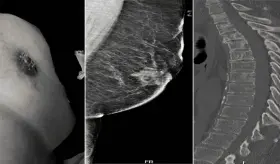

Paciente con cáncer de mama triple negativo metastásico fungiante, que tras progresar a dos líneas de quimioterapia, logró una respuesta clínica significativa con radioterapia ultrahipofraccionada

El melanoma lentiginoso acral es una variante agresiva y difícil de re...

El manejo incluyó quimioterapia con paclitaxel e inmunoterapia con cemiplimab, logrando más de 18 meses de control clínico antes del deterioro final.